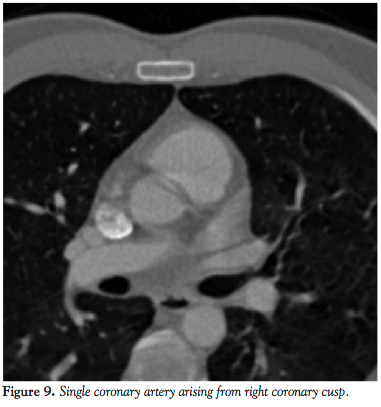

Case report 2. A 46-year-old male had a history of hyperlipidemia, diabetes mellitus, mitral regurgitation, hypertension, and chest pains. His physical examination was unrevealing. Cardiolite stress test revealed apical scar and 2-D echocardiogram revealed an ejection fraction 55% with mild mitral regurgitation. A cardiac catheterization was performed due to persistent chest pains and revealed an anomalous coronary artery where the entire left coronary artery and RCA arose from one origin at the right coronary cusp. No obstructive lesions were noted.

A subsequent CT angiography was obtained to delineate the course of this vessel. A 64-slice CT scan revealed that the left coronary artery coursed in between the aorta and pulmonary artery. In view of his ongoing chest pains, with a high risk of myocardial infarctions (MI), fatal arrhythmias, and sudden death, CABG was recommended.

We described 2 cases of a single coronary anomaly with 2 distinct anatomical patterns. One case had a single coronary artery arising from the right coronary cusp giving off the left main coronary artery, which passed anteriorly to the pulmonary artery and branched into the LAD and circumflex artery. In the other case, the left main coronary artery arose from the right coronary cusp and passed in between the aorta and pulmonary arteries.

The second case illustrates the left main coronary artery arising from the RCA and passing in between the aorta and main pulmonary trunk. This anatomy corresponds to the IIB2 classification of the isolated coronary artery anomalies.5 In this case, the risk of MI, fatal arrhythmias, syncope, and sudden death is significantly increased and it is postulated that this may occur as a result of an expansive effect of the aorta during exercise. This leads to the compression of the left coronary artery, which results in chest pains, angina, arrhythmias, and even sudden death. Our patient was found to have had a negative noninvasive work-up for coronary artery disease but in spite of this, had persistent recurrent chest pains for which coronary artery angiography was recommended.